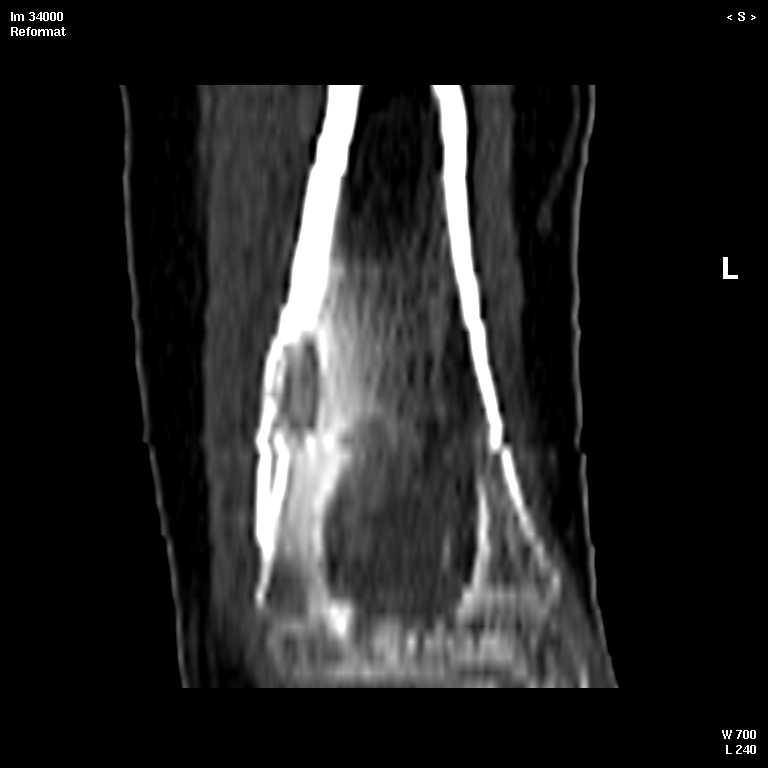

С подозрением на хондрому большеберцовой кости левой голени выполнена компьютерная томография. На серии томограмм получены изображения дистальных отделов левой голени. В дистальном метафизе на уровне нижней трети по латеральному краю определяется кортикальный очаг деструкции размерами 1,3x0,5x0,8 см. На уровне очага деструкции отмечается истончение кортикального слоя, без признаков его разрушения. Кость на уровне очага вздута. Структура окружающих мягких тканей не нарушена, объемных образований не определяется. Крупные нервные стволы и просветы крупных сосудов хорошо дифференцируются. Кожа и подкожно-жировая клетчатка не изменены.Заключение: КТ - признаки кортикального остеолитического очага деструкции в дистальном отделе метафиза левой большеберцовой кости без признаков разрушения кортикального слоя (остеогенная саркома?).19.11.2002 г. осмотрена онкологом, выставлен диагноз: саркома левой большеберцовой кости?Лабораторные исследования: - ОAK от 06.11.2002 г. - L - 11,3х109; эр. - 4,47хЮ12; НЬ - 117 гр./л; Ht - 33,6%; тр. -208x109; СОЭ - 38 мм./час, э-1; п-7; с-55; м-4; л-33.В отделении детской онкологии 11.12.02 выполнена операция: секвестр-некрэктомия н/3 левой большеберцовой кости.Послеоперационный период без осложнений.Проведено лечение. Линкомицин 150 мгхЗ р./д., обезболивание (анальгин, димедрол). Швы сняты 23.12.02, заживление первичным натяжением.Получен результат гистологического исследования: хронический остеомиелит. Данных за онкопроцесс нет.На приеме врача ортопеда поликлиники с жалобами на усиление болевого синдрома 03.01.03. Наложена задняя гипсовая лангета. Назначен противовоспалительная терапия, препараты Са и кальцийтониновые препараты. На фоне проводимого лечения болевой синдром купировался. На серии рентгенограмм (январь-февраль-март) На нижней трети левой большеберцовой кости наличие дополнительного кортикального очага диструкции с размерами 1.5x0,5 см., в динамике отмечается увеличение в размерах.С подозрением на рецидив хронического остеомиелита большеберцовой кости левой голени выполнена компьютерная томография.19/03/2003 На серии томограмм получены изображения дистальных отделов нижней трети левой голени и мягких тканей.В метафизе определяется очаг деструкции с четкими, неровными контурами, неоднородной структуры, за счет костных балок, размерами 1.8x1.8x2,4 см, плотностью 29 ед Н.В дистальном методиафизе. по латеральному краю, определяется кортикальный очаг деструкции, размерами 0,6x0,5x2,0 см, неоднородной структуры, за счет наличия фиброзных и костных балок, кортикальный слой истончен, без признаков разрушения.Структура окружающих мягких тканей не нарушена, объемных образований не определяется. Крупные нервные стволы и просветы крупных сосудов хорошо дифференцируются.Кожа и подкожно-жировая клетчатка не изменены.ЗАКЛЮЧЕНИЕ:КТ-картина состояния после операции. Формирование постоперационной, внутрикостной кисты. КТ-признаки объемного образования нижней трети левой большеберцовой кости, вероятнее всего фиброзная дисплазияРЕКОМЕНДАЦИИ: МРТ левого голеностопного сустава с захватом нижней трети голени.Лабораторные исследования: OAK от 05.03.2003 г. - L v 7.0х109; эр. - 4,74хЮ12; НЬ - 130 гр./л; Ht - 37%; тр. -274x109; СОЭ - 4 мм./час, э-1; п-1; с-53; м-3; л-42.Вопросы: уточнение диагноза? (хр.остеомиелит, обострение? Или все таки онкопроцесс) какие исследования провести? тактика лечения? КТ-снимки во вложении. Заранее благодарен!С уважением, Н.П.Козел.